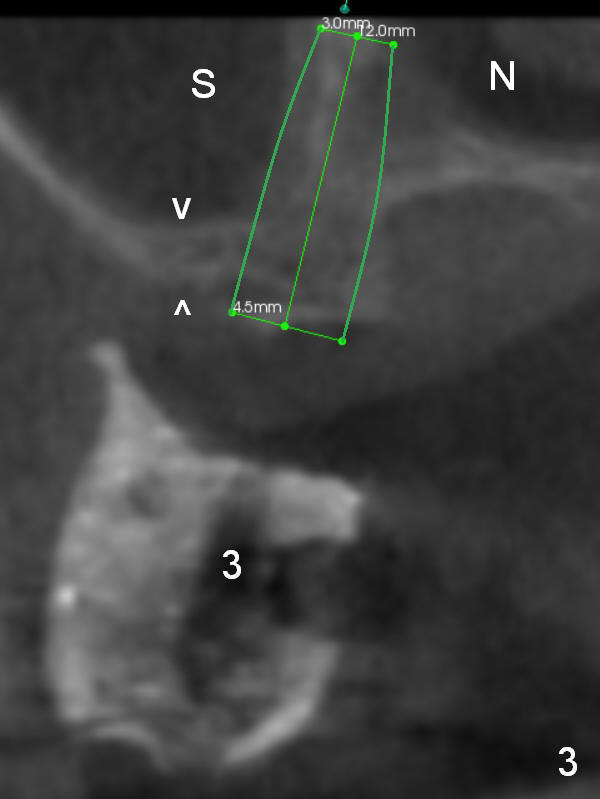

Fig.3: CBCT coronal section at the site of #3. An implant is going to be placed in the bone the sinus (S) and the nasal cavity (N) following bone expansion. In contrast the sinus floor (between arrowheads) appears to be too thin for internal sinus lift. The axis of the implant is favorable for restoration.

In fact the bone available for untraditional implant placement is more exactly located between the sinus and the palate (Fig.3' pink dashed line).

Since it is narrow, it should be expanded prior to implant placement. A small pilot drill, 1.2 or 1.6 mm in diameter, is used to initiate bone expansion (Fig.3'' red line).